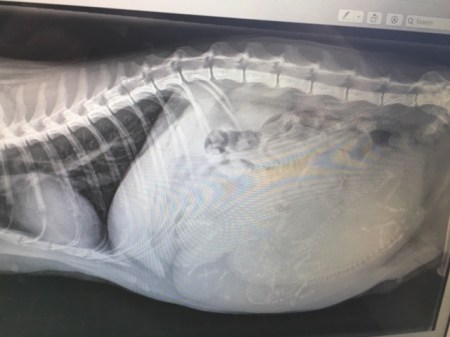

And yes, Baby Girl was VERY pregnant. How many kittens do you see??

And here is her broken front leg.